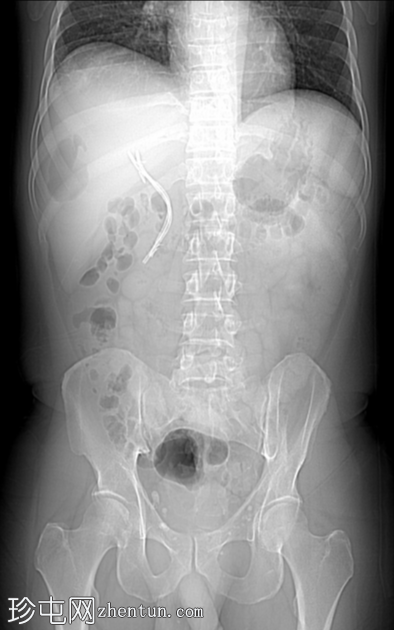

7.png

冠状位增强扫描

门静脉期

增强扫描图像显示囊肿边缘强化,周围可见晕环,呈双靶征。

该患者近期行胆囊切除术及胆总管支架置入术,近期主诉右上腹疼痛及发热。影像学表现符合医源性化脓性肝脓肿介入治疗后的典型特征,右肝叶囊性病变可见管腔内气体和气液平面,增强扫描后边缘强化,并可见经典的双靶征。患者接受了超声引导下经皮穿刺引流术治疗。遗憾的是,培养结果尚未公布。

整个病灶周围可见节段性或外周性短暂性灌注障碍。